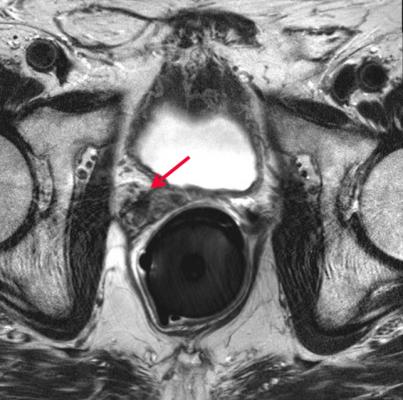

Den — an associate professor of radiation oncology, cancer biology and urology at Jefferson — and colleagues analyzed data from 12 randomized controlled trials of external beam radiation treatment for men with non-metastatic prostate cancer, which included a total of 6,884 patients. By pooling data from multiple clinical trials, the researchers were able to see trends that would not have been apparent in the individual studies.

Rather than use the typical proxy for patient improvement, the prostate cancer antigen (PSA) test, the researchers looked at long-term outcomes such as the development of metastatic cancer and death from cancer. They found that while PSA levels decreased as patients received higher doses of radiation, the overall survival and incidence of metastases, among other measures, did not improve.